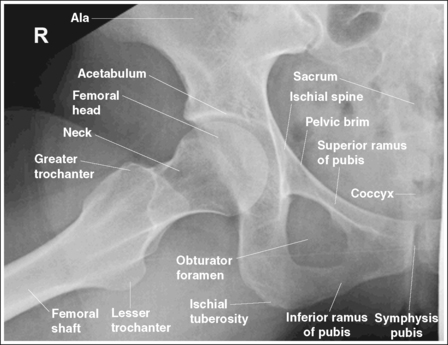

Hip: Anteroposterior Projection

The pelvis demonstrates an AP projection. The ischial spine is aligned with the pelvic brim, the sacrum and coccyx are aligned with the symphysis pubis, and the obturator foramen is open.

• An AP projection of the hip is obtained by placing the patient supine on the imaging table with the legs extended (Figure 7-3). To ensure that the pelvis is not rotated, judge the distances from the anterior superior iliac spines (ASISs) to the imaging table. The distances on each side should be equal.

• Detecting pelvis rotation. Rotation on an AP hip projection is initially detected by evaluating the relationship of the ischial spine and the pelvic brim, the alignment of the sacrum and coccyx with the symphysis pubis, and the degree of obturator foramen demonstration. If the patient was rotated toward the affected hip, the ischial spine is demonstrated without pelvic brim superimposition, the sacrum and coccyx are not aligned with the symphysis pubis but are rotated away from the affected hip, and the obturator foramen is narrowed (see Image 1). If the patient has been rotated away from the affected hip, the ischial spine is not aligned with the pelvic brim but is demonstrated closer to the acetabulum, the sacrum and coccyx are not aligned with the symphysis pubis, but are rotated toward the affected hip, and the obturator foramen is widened (see Image 2).

The femoral neck is demonstrated without foreshortening, the greater trochanter is in profile laterally, and the lesser trochanter is superimposed by the femoral neck.

• Accurate leg positioning. To demonstrate an AP hip projection with the femoral neck shown without foreshortening and the greater trochanter in profile, the patient's leg should be internally rotated until the foot is angled 15 to 20 degrees from vertical and the femoral epicondyles are positioned parallel with the imaging table (Figure 7-4; see Figure 7-1). A sandbag or tape may be needed to help the patient maintain this internal leg rotation.

The femoral head or neck is at the center of the exposure field. The acetabulum, greater and lesser trochanters, femoral head and neck, and half of the sacrum, coccyx, and symphysis pubis are included within the collimated field. Any orthopedic apparatus located at the hip are included in their entirety.

• A perpendicular central ray is centered 1.5 inches (4 cm) distal to the midpoint of a line connecting the ASIS and superior symphysis pubis, to center the hip joint in the center of the exposure field, and a perpendicular central ray is centered 2.5 inches (6.25 cm) distal to the midpoint of a line connecting the ASIS and superior symphysis pubis to place the femoral neck in the center of the exposure field (Figure 7-6). Center the IR to the central ray and open the longitudinal collimation enough to include the ASIS and any hip orthopedic apparatus. Transversely collimate to the patient's midsagittal plane and within 0.5 inch (1.25 cm) of the lateral hip skin line. Including half of the sacrum, coccyx, and symphysis pubis within the exposure field provides a way to evaluate pelvic rotation.